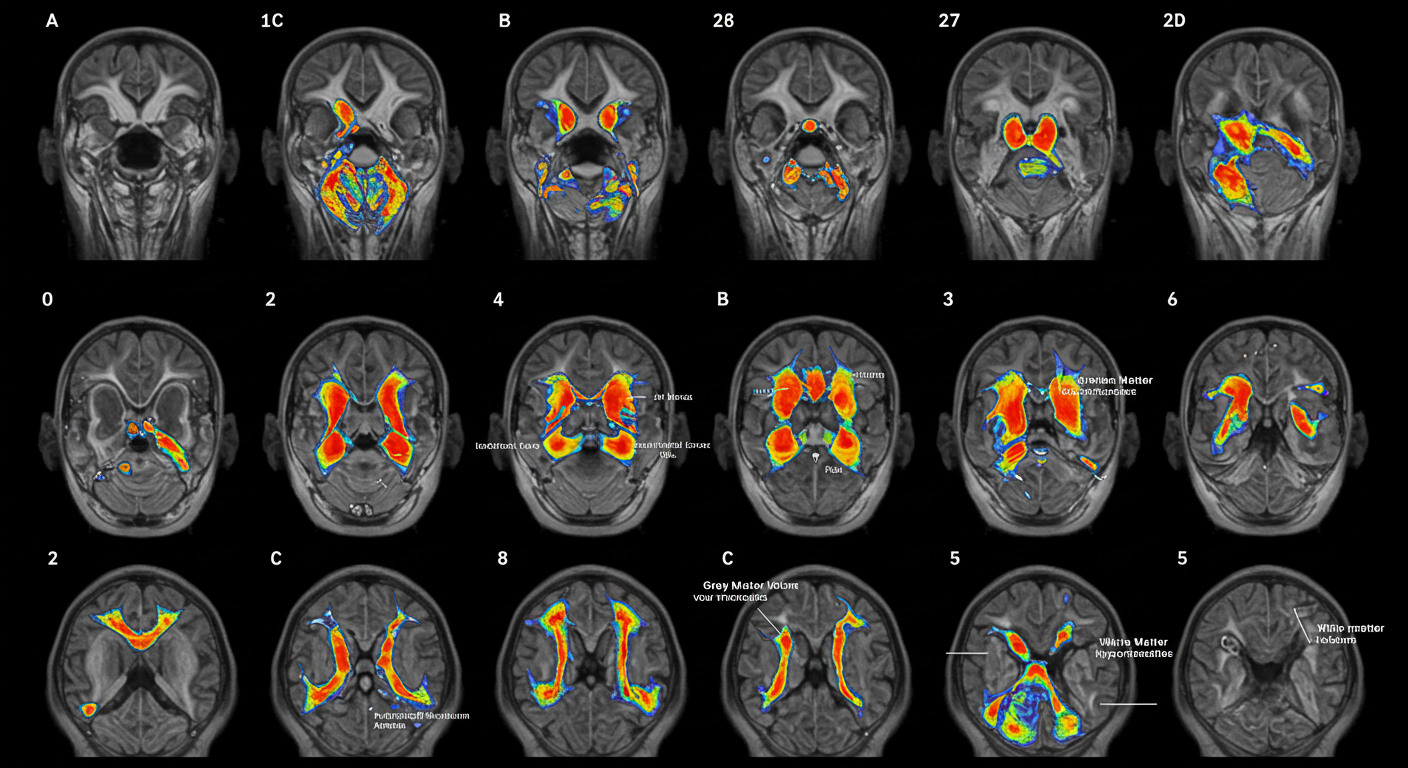

- 뇌 MRI 변화: MRI 검사 결과에서도 보행 속도가 느린 사람은 뇌가 더 작고, 신피질은 더 얇고 상대적으로 백질이 많아 인지 기능 저하가 관찰되었습니다.